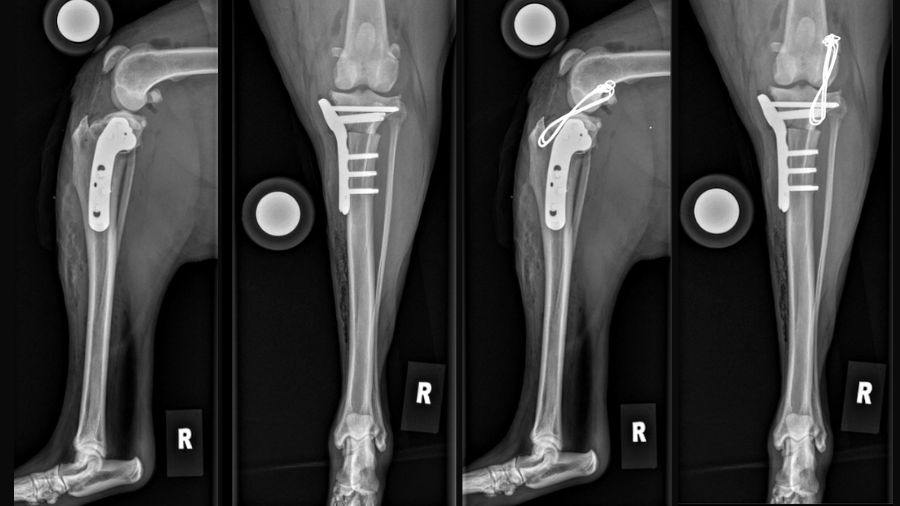

Planning the lateral suture – Step 1 TPLO premormed – Step 2 Nylon 40 lbs as lateral suture:

TPLO without the Lateral Suture – Rendering the same TPLO with nylon suture, CC and ML view:

Surgical procedure:

TPLO was performed using standard technique, achieving a tibial plateau angle of 4.3° post operatively. However, intraoperative assessment following TPLO completion revealed persistent rotational instability, particularly internal rotation. Two strands of 40-pound nylon lateral suture was placed using a modified extracapsular technique to address the residual rotational laxity.

The patient followed a standard TPLO rehabilitation protocol with excellent compliance. At 12 weeks post-surgery, radiographs confirmed complete osteotomy healing with no evidence of implant complications. Functional assessment revealed complete resolution of instability with return to normal activity levels.